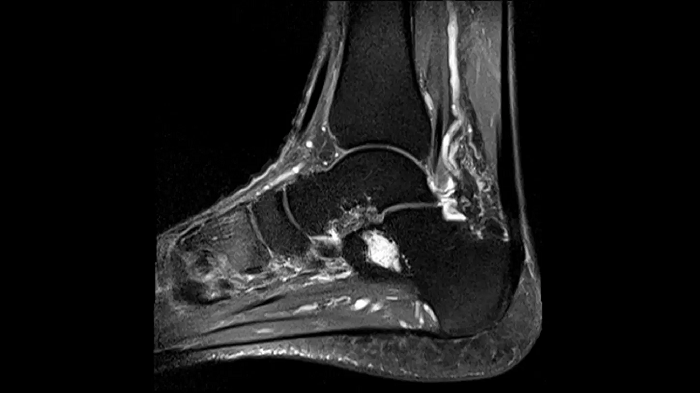

Ankle

Ankle - PD TSE FatSat

Even in demanding anatomies such as ankle with Contour S Coil, achieve optimal image quality.

Image Courtesy: University Hospital Erlangen, Germany | Image-ID: 4aaaa0381